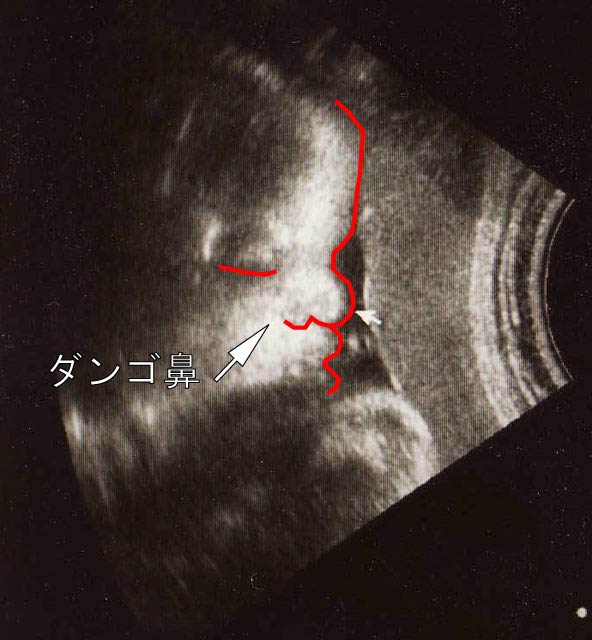

2月1日から、産休に入りました。産前6週前から産後8週後までの休暇です。現在、2月8日で35週目に入りました。33週目の時に撮ったエコーをUPします。皆で笑ってあげてください。鼻の丸さ爆裂中《横顔・・・ダンゴ鼻》《下から・・・ブタ鼻》